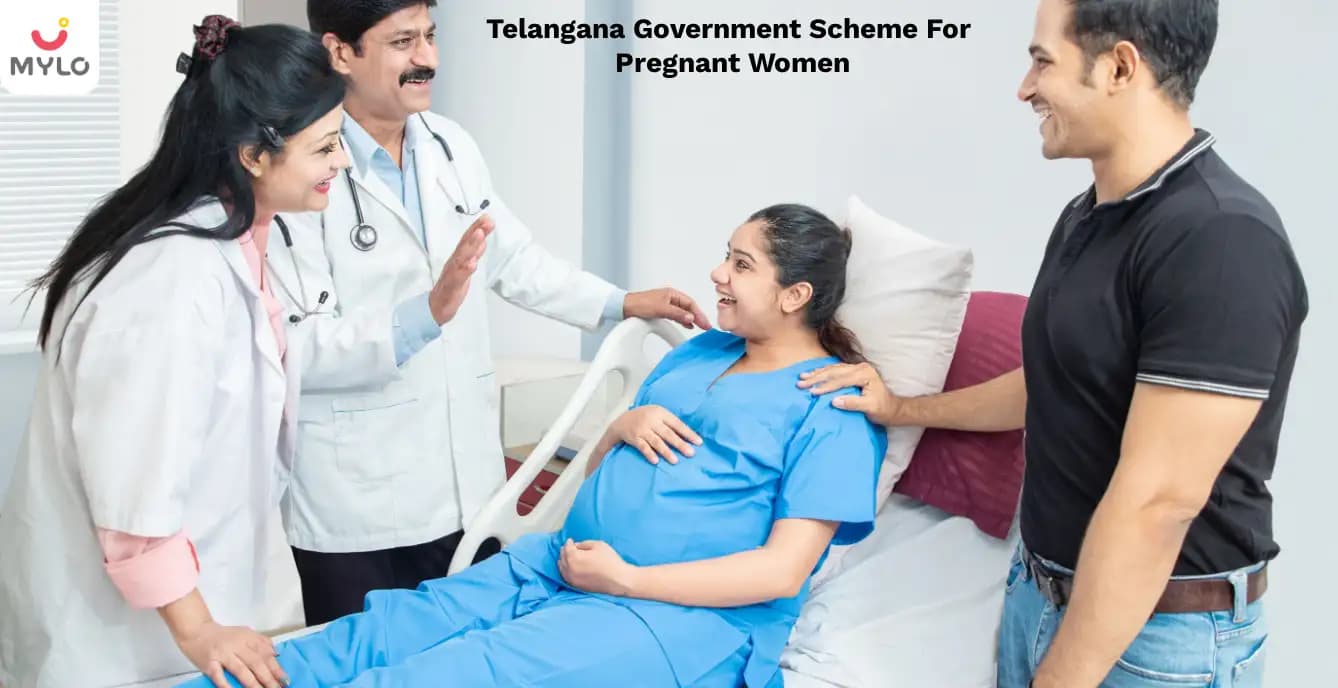

Telangana Government to Offer Financial Assistance of Rs. 12,000 & KCR Kit to Pregnant Women